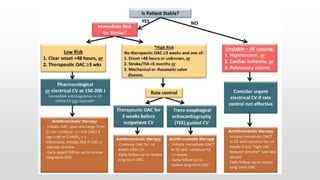

This document discusses various cases of collapse and syncope. It defines collapse as transient loss of consciousness with loss of postural tone and full recovery. Syncope is defined as loss of postural tone with or without loss of consciousness and full recovery. It then discusses the multiple potential causes of collapse and syncope including toxicological, cardiac conduction abnormalities, structural cardiac issues, autonomic dysfunction and more. It then goes through 9 case examples, discussing important questions to ask, potential tests and interventions for each case.